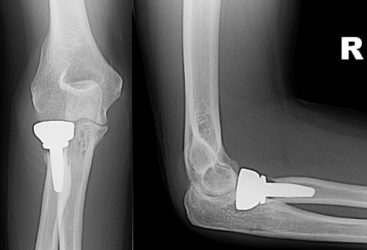

2c. X-rays after radial head replacement and ligament repair